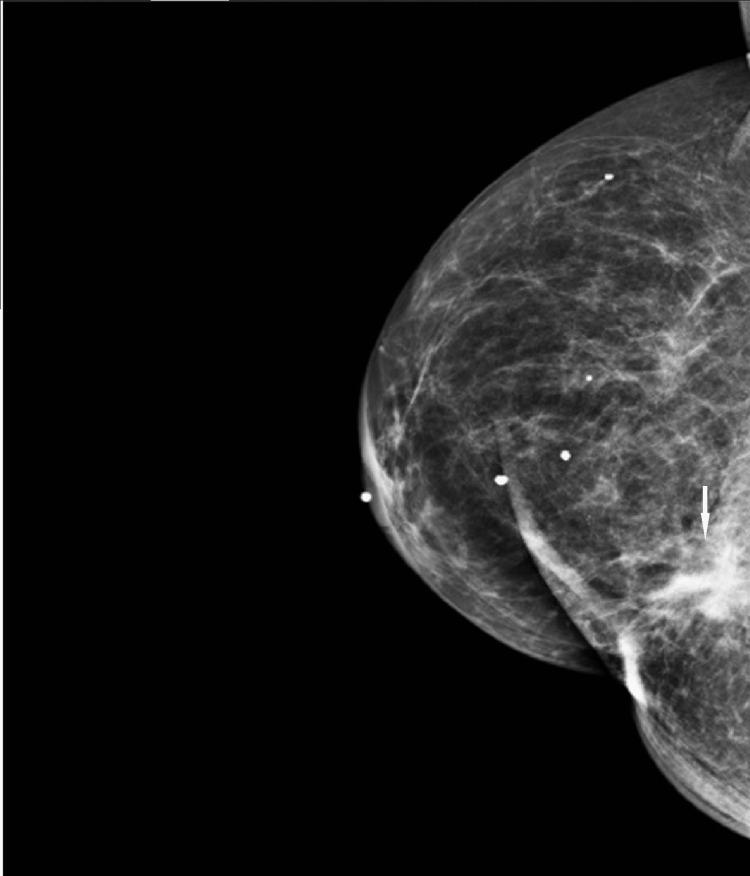

We describe a case of pathology-proven invasive lobular breast cancer (ILC) arising in a scar over 15 years after lumpectomy for previous invasive ductal carcinoma (IDC). The tumor was detected on screening mammography as a new focal asymmetry at the scar site and confirmed at diagnostic mammography. Ultrasound demonstrated an irregular, shadowing, hypoechoic mass at the scar site. Ultrasound-guided biopsy revealed poorly differentiated invasive lobular carcinoma. MRI and CT showed an irregular mass with pectoralis muscle invasion. Multimodality imaging findings are described. This is the first case to our knowledge reporting multimodality imaging findings of a breast cancer developing at the site of a surgical scar that is histologically different from the originally resected cancer.

我们描述了一例经病理证实的浸润性小叶乳腺癌(ILC)病例,该病例发生于先前因浸润性导管癌(IDC)行肿块切除术后15年以上的瘢痕处。肿瘤在筛查乳腺X线摄影中被检测为瘢痕部位新出现的局灶性不对称,并在诊断性乳腺X线摄影中得到证实。超声显示瘢痕部位有一个不规则、有阴影、低回声肿块。超声引导下活检显示为低分化浸润性小叶癌。MRI和CT显示有一个不规则肿块,侵犯胸大肌。描述了多模态成像结果。据我们所知,这是首例报告手术瘢痕部位发生的组织学上与最初切除的癌症不同的乳腺癌的多模态成像结果的病例。